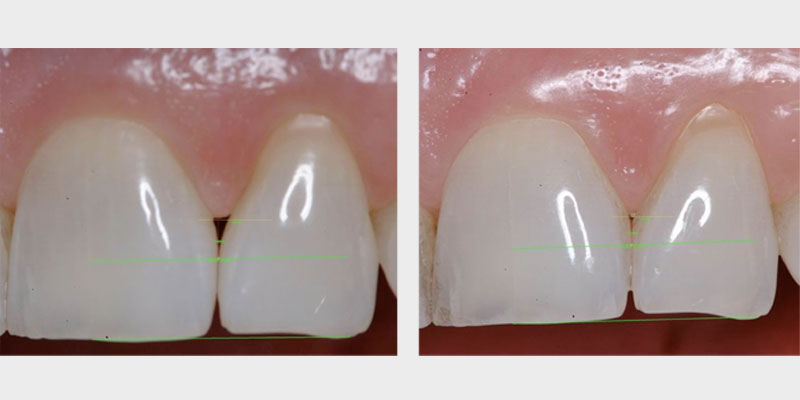

The primary goal of periodontal treatment is the maintenance of health, function and esthetics of the natural dentition and supporting structures. When necessary, this includes tooth and tissue replacement with regeneration and dental implants (Figs. 3A, 3B).

Periodontal regeneration includes the recreating of periodontal ligament, cementum and alveolar bone along the previously diseased and denuded root surface. The evidence supporting guided tissue regeneration is vast and growing. For decades dental surgeons have been using, with high levels of predictability, resorbable and non-resorbable barrier membranes in passive tissue engineering around teeth and dental implant dehiscence and fenestrations.3, 4 By employing active tissue engineering, new levels of predictability and success can be reached to resolve hard and soft tissue, periodontal and other orofacial defects.